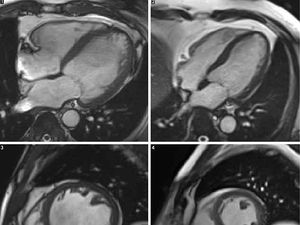

detikHealthSabtu, 26 Mei 2018 17:10 WIB

Konsumsi minuman beralkohol sudah diketahui memiliki efek buruk bagi jantung. Nah, gambar ini menunjukkan bagaimana bentuk jantung peminum alkohol.